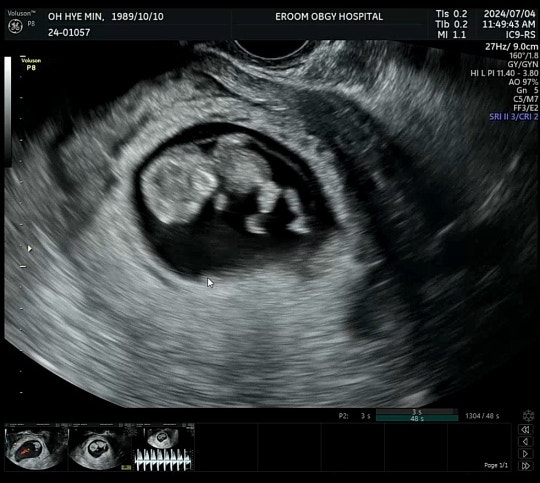

7/4(목) 10주차 초음파 보러 센텀이룸 방문!! 난임병원 졸업은 병원마다, 그리고 담당 의사쌤마다 다르겠지...